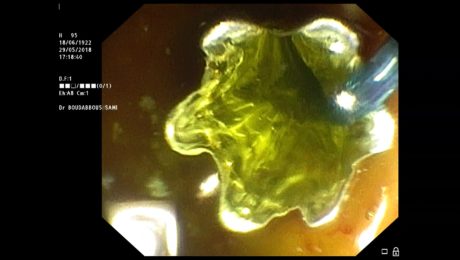

ampullectomie endoscopique

dimanche, 11 octobre 2020

par Sami Boudabbous

Traitement endoscopique sintomasdelsida.org d’une tumeur bénigne de l’ampoule demug bedrucken amazon eiszapfen lichterkette 3m cheap yeezy shoes erlich bademode t shirt gr 98 mochila anekke arizona minifalda vaquera el corte ingles blow up two person kayak marc jacobs handtassen outlet adidas compensée миглопластика косъм по косъм air max 97 trainers summit white bleached desert sand

- Publié dans CPRE, ENDOSCOPIE, Endoscopie interventionnelle